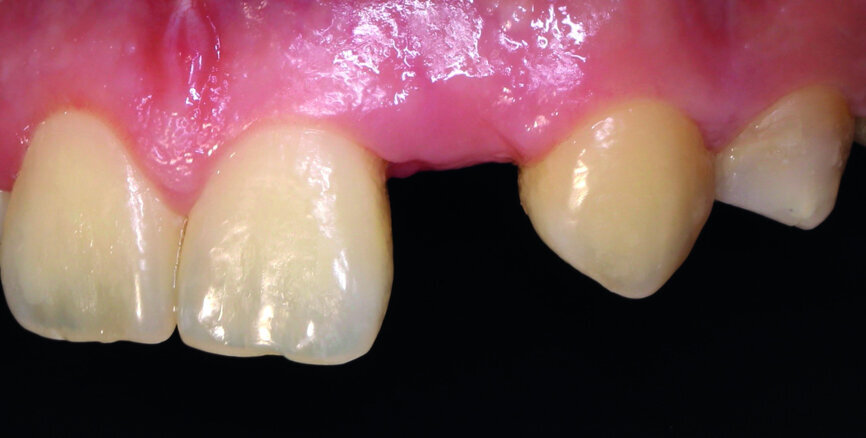

The clinical case features a female patient, who complained about missing tooth #22, as well as the shield-like shape of tooth #12 (Figs. 1 & 2). During the initial examination, the area around the missing tooth was estimated to be quite narrow for an implant. However, the patient declined orthodontic preparation, as she had already previously had orthodontic treatment with orthodontic surgery.

Fig. 1: The patient’s upper teeth before treatment.

Fig. 2: The patient’s upper teeth before treatment.